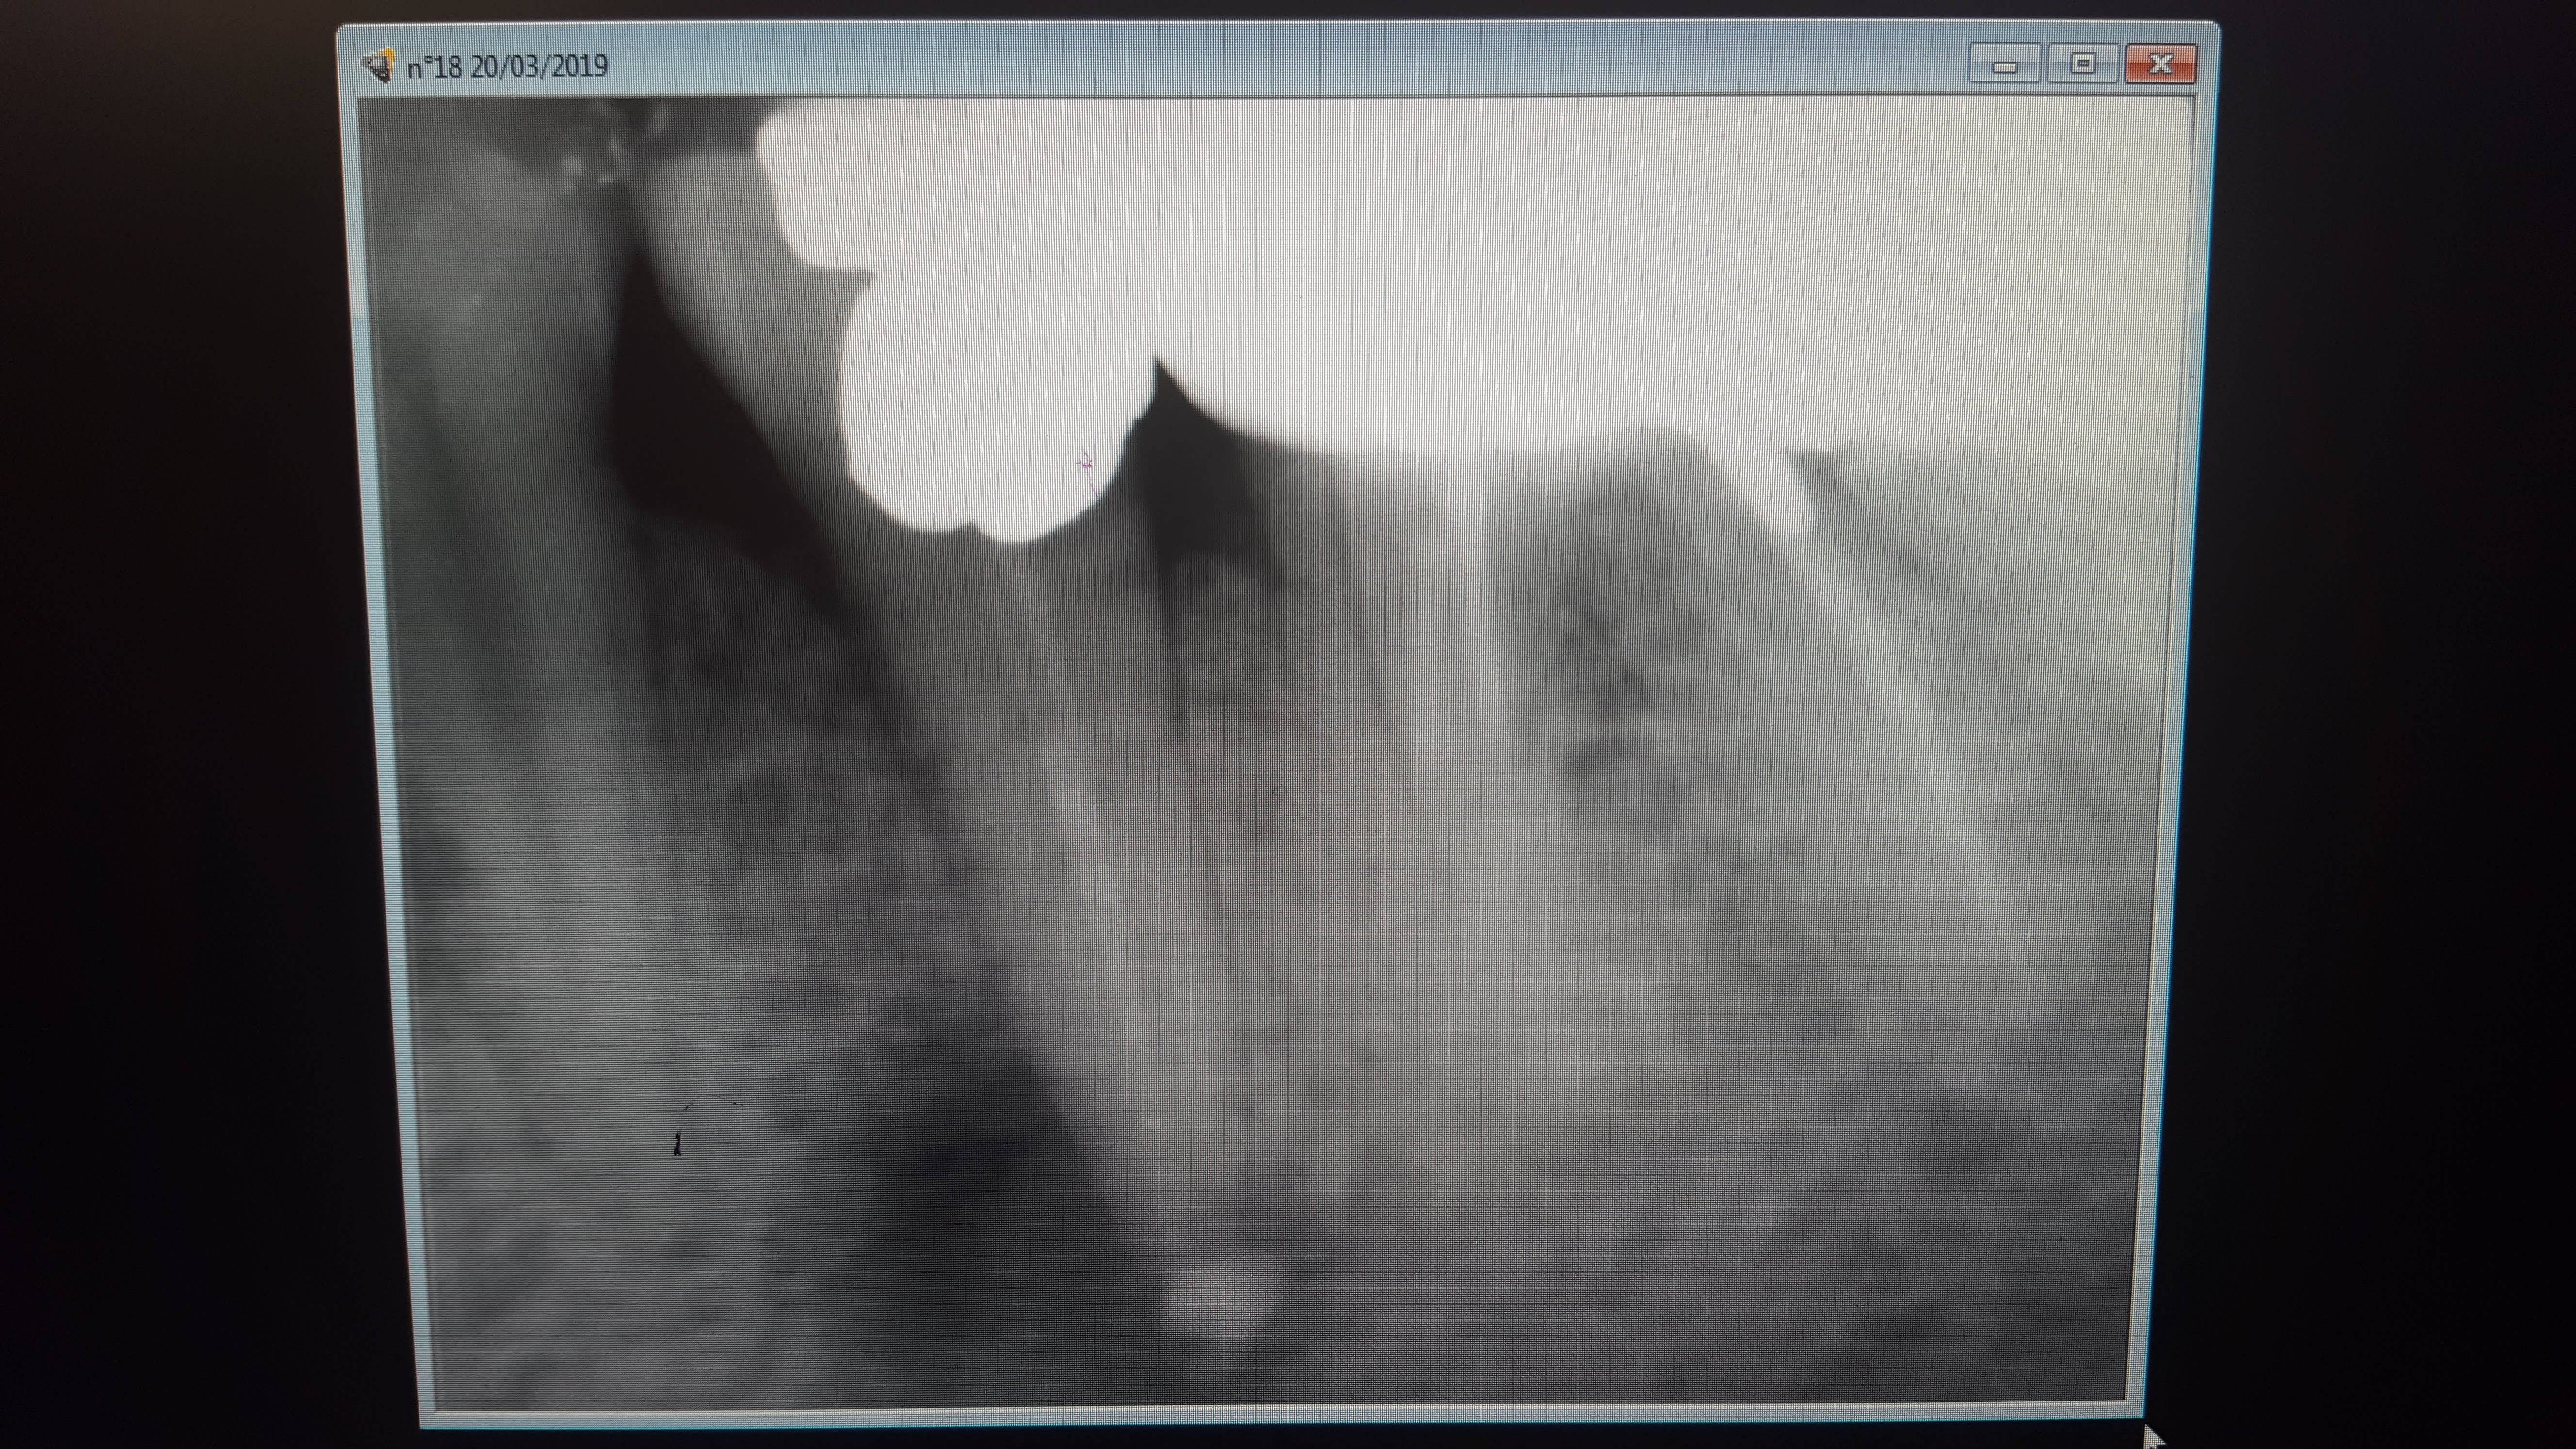

Je fais la radio de contrôle et je vois un gros dépassement d'hyca ,juste injecté à la seringue, pas de lentulo,au niveau de la lésion apicale visible radiologiquement.

Le canal dentaire n'est pas en cause, l'hyca est cantonné dans la lésion qui remonte vers la furcation.

j'ai injecté l'hyca avec seringue mais peut-être que l'embout était bloqué dans la racine et donc légère surpression?

Personnellement j'aime bien qu il y ait un petit dépassement d'hycal.

J'ai l'impression que ça aide à la baisse rapide de la charge infectieuse.

En revanche les apex semblent grands ouverts...